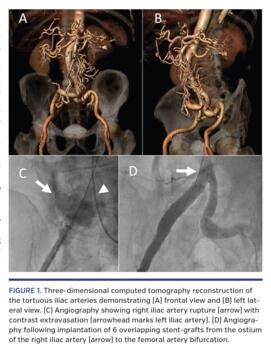

An 82-year-old male with severe symptomatic aortic stenosis underwent elective transfemoral transcatheter aortic valve replacement (TAVR). Preprocedural computed tomography angiography revealed marked tortuosity of the femoral and iliac arteries (Figures 1A and 1B). During delivery of a 29 mm Evolut R valve (Medtronic), the patient sustained pulseless activity. The valve was removed and replaced with a 16 Fr sheath. Contrast injection revealed rupture of the proximal iliac artery (Figure 1C). A 12 x 60 mm Fluency stent-graft (Bard Peripheral Vascular) was immediately implanted at the ostium of the iliac artery and the patient received fluid resuscitation as well as infusion of norepinephrine and red blood cells. Following valve delivery via the stent-graft and implantation within the aortic annulus, the patient remained hypotensive; repeat angiography revealed persistent contrast extravasation distal to the site of implantation of the stent-graft. Hemostasis was achieved following implantation of 5 additional overlapping stent-grafts extending to the femoral artery bifurcation (Figure 1D). The patient recovered hemodynamically and was discharged to his home with no adverse clinical sequelae. This case illustrates the feasibility of percutaneous vascular repair following severe vascular injury during TAVR.